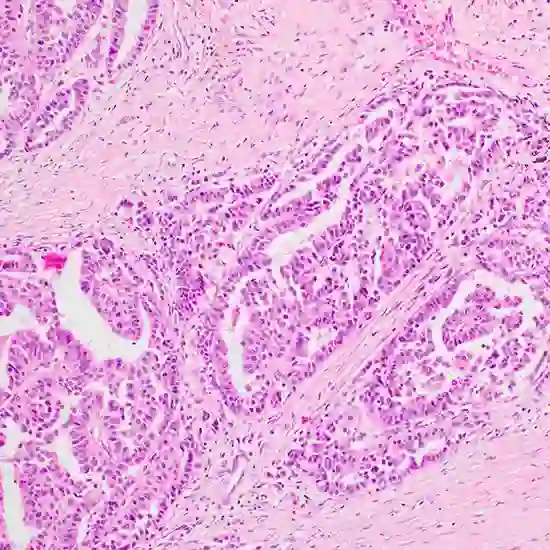

Papillary carcinoma of the breast is a rare type of breast cancer that is characterized by the presence of finger-like projections or papillae in the tumor cells when viewed under a microscope. Papillary carcinoma accounts for only a small percentage of all breast cancers, typically less than 1-2% of breast malignancies.

Diagnosis of papillary carcinoma typically involves a combination of physical examination, imaging tests (such as mammography, ultrasound, or MRI), and biopsy to confirm the presence of papillary carcinoma cells. Papillary carcinoma is typically characterized by the presence of finger-like projections or papillae lined by tumor cells, which can be seen under a microscope.